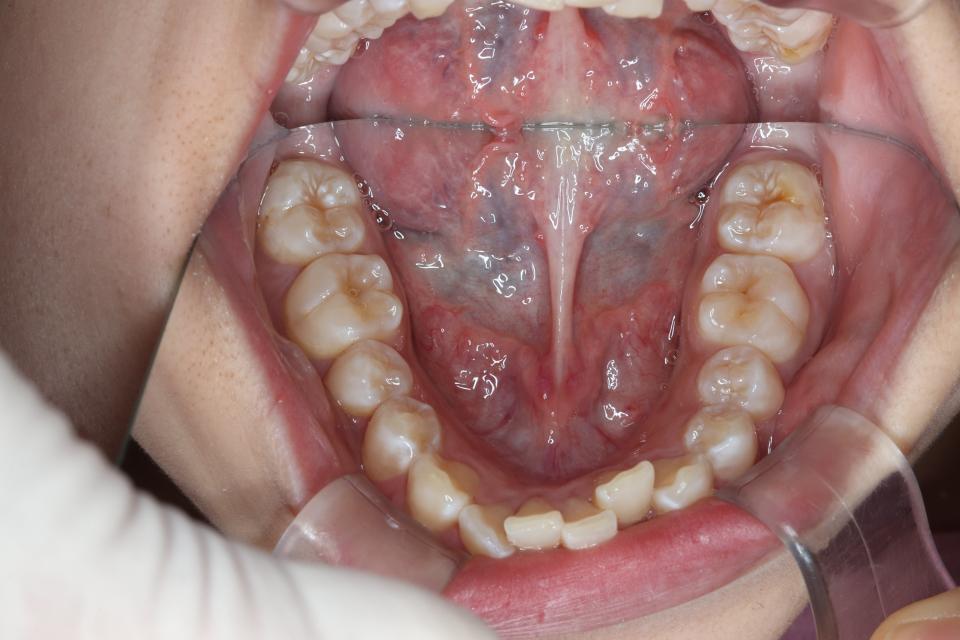

がたがた(叢生)のワイヤー矯正治療例(抜歯あり)

矯正治療前

20代女性の患者さんです。

上左右4番抜歯をして、上下の歯にワイヤー(マルチブラケット装置)をつけて治療しました。

きれいに並びきるために歯のやすりがけ(IPR)も行っています。